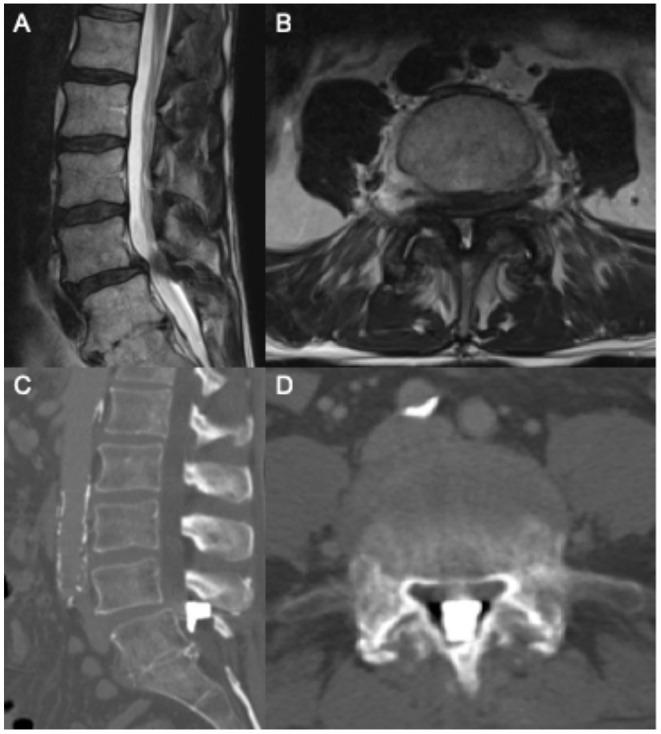

We carried out a retrospective review at our institution of neurosurgical consultations for patients with hardware complications following the interspinous device placement procedure. Eight cases within a 3-year period were identified, and patient characteristics and management are illustrated. The series describes the migration of hardware, spinous process fracture, and worsening post-procedural back pain.

我们对本院接受棘突间装置置入术后出现硬件并发症患者的神经外科会诊进行了回顾性研究。在3年期间内确定了8例病例,并阐述了患者特征及治疗情况。该系列描述了硬件移位、棘突骨折以及术后背痛加重的情况。